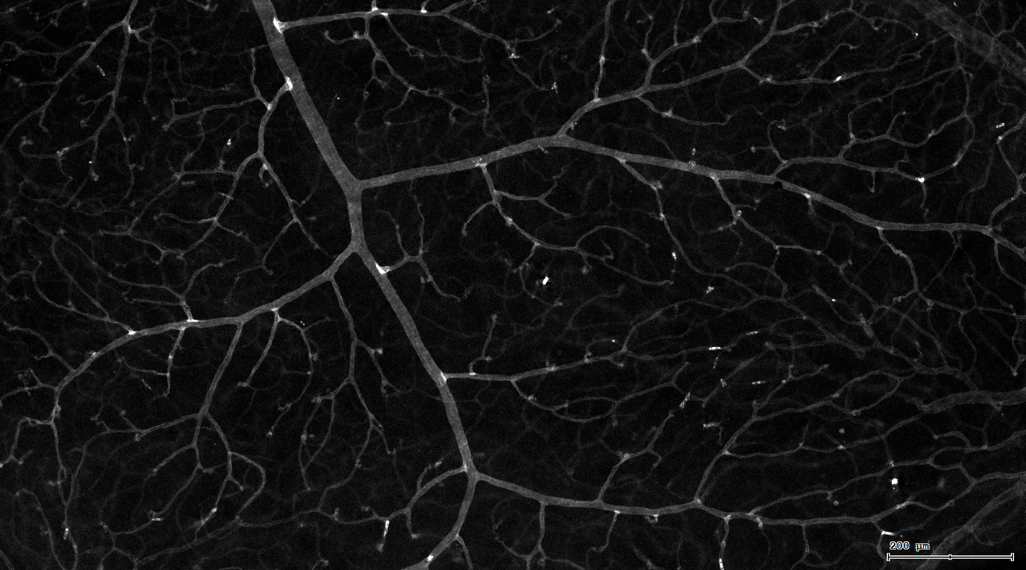

4. 膜识别FITC染色信号的区域确定神经纤维,并对不同长度神经纤维进行分类。

5. 识别血管的Texa Red染色区域面积及强度。

7. 根据毛细血管亮斑的识别结果,统计新生小血管数量。

血管识别:根据Texa Red通道进行识别,并去除面积小的及非同一焦面的血管,仅对确定的清晰的同一焦面的大血管进行面积统计。